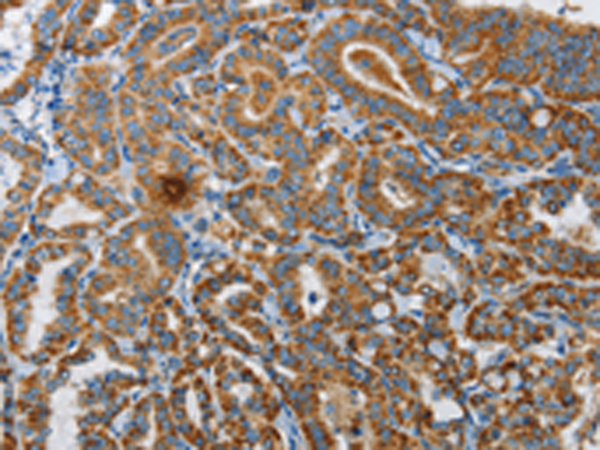

分类: 科研抗体货号: P04601别名: HUPF1; NORF1; RENT1; smg-2; pNORF1应用: WB,IHC反应种属: Human, Mouse